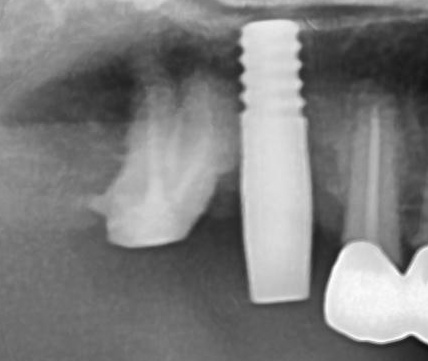

しっかりとインプラント埋め込まれた後は、動揺がないか、噛んだ時に当たらないかなどを確認して、最後にパノラマ写真を撮影して今回のオペは終了となりました。